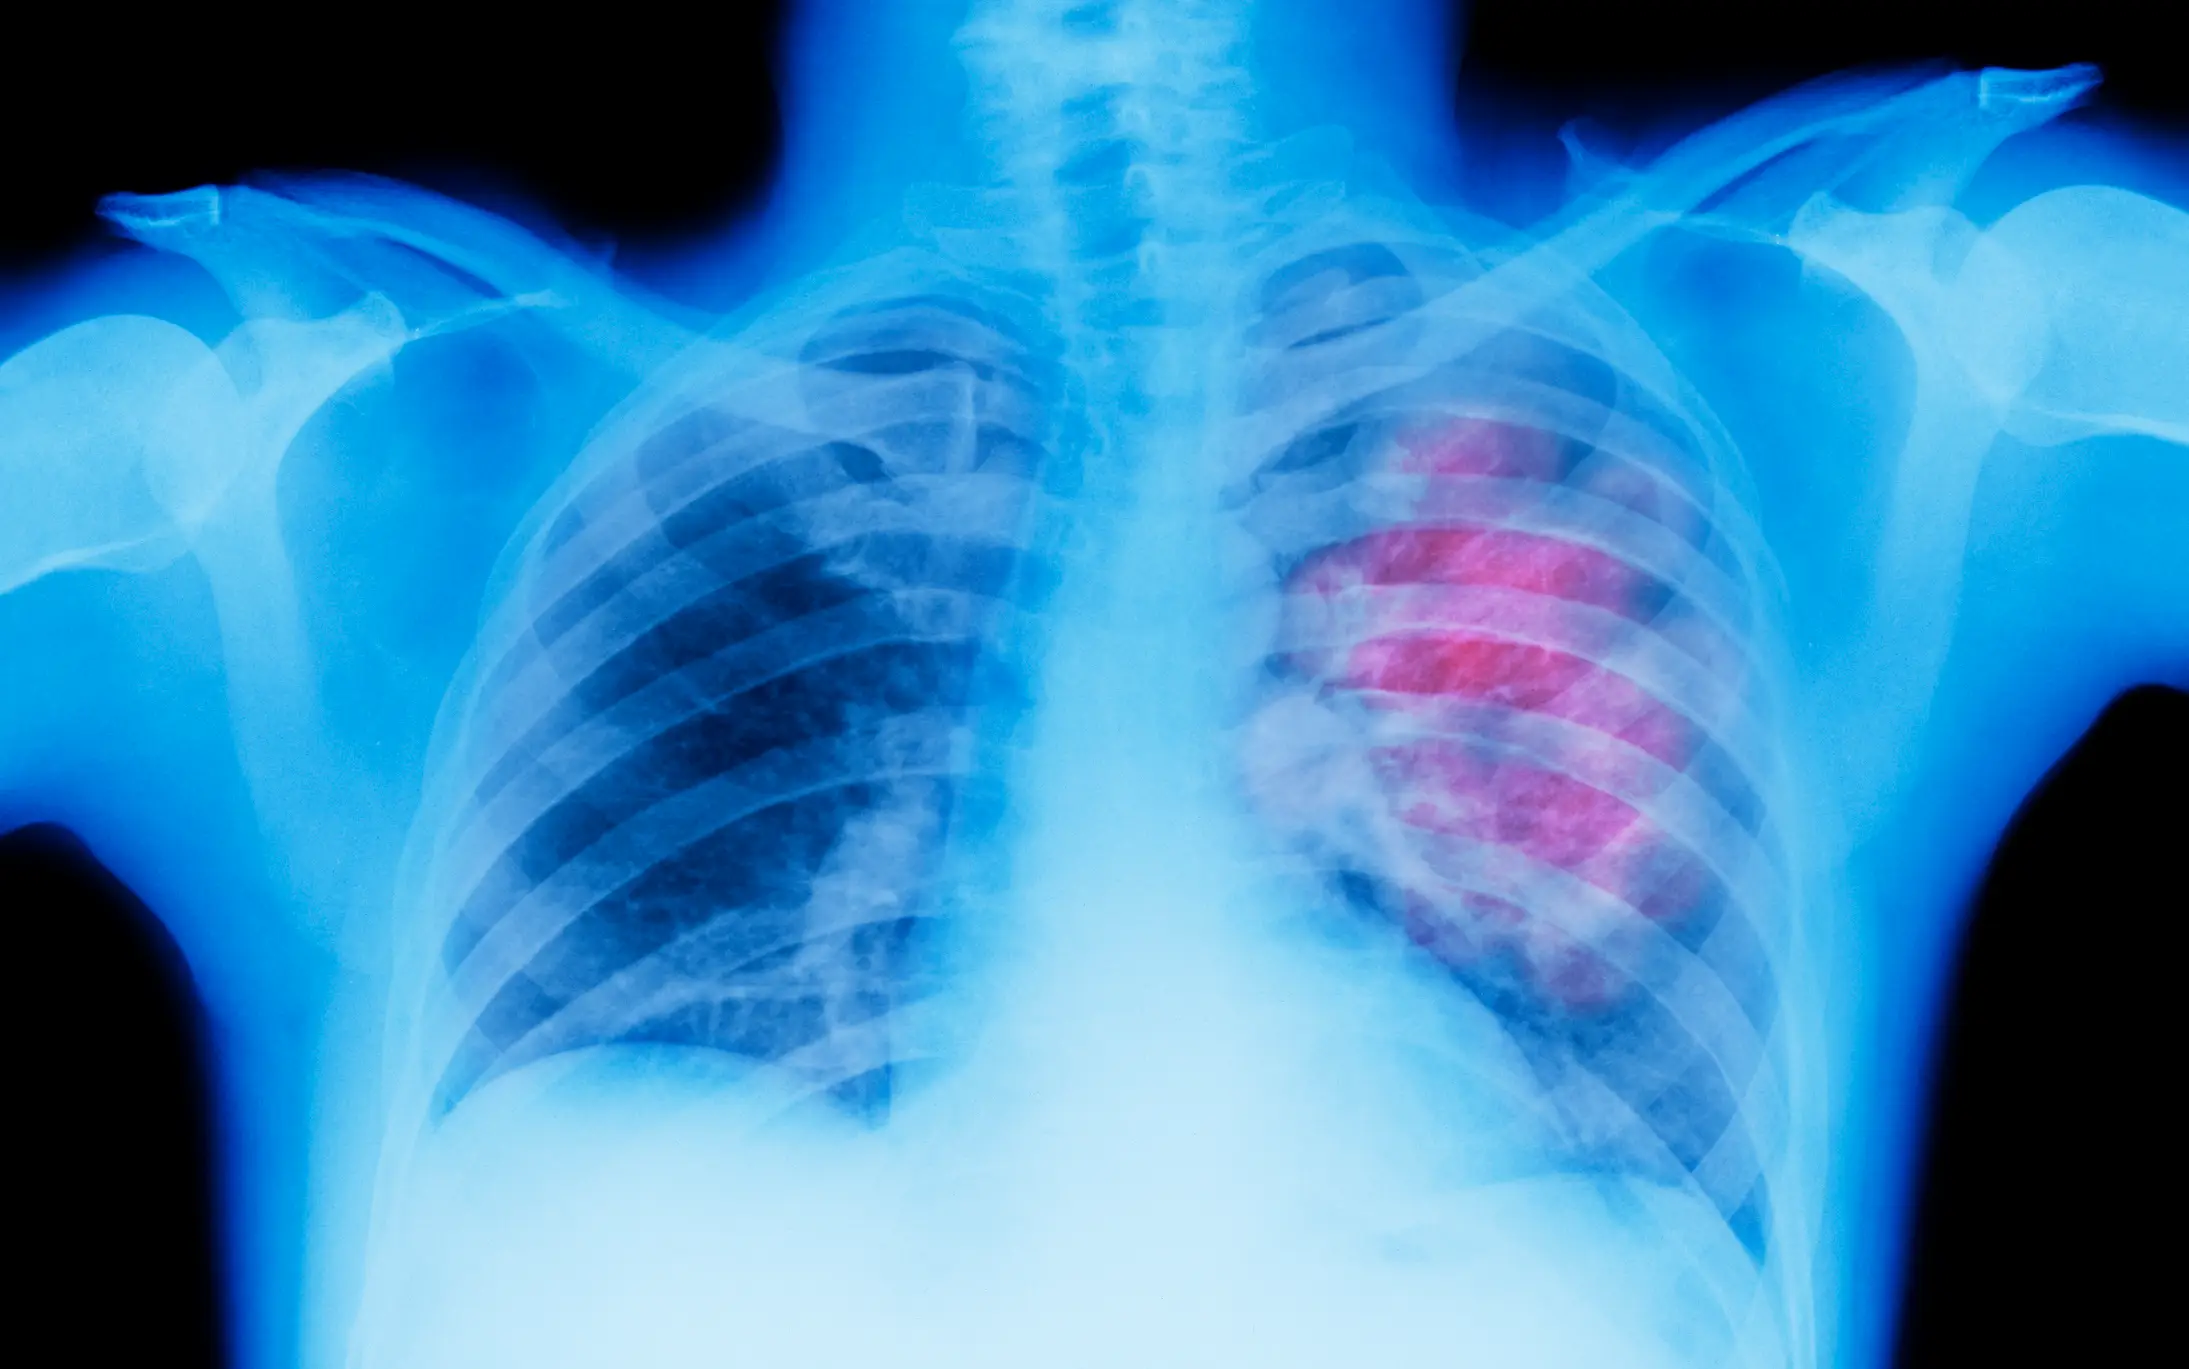

The change can indicate serious problems with the lungs or heart, so if you notice it, it's important to seek medical advice.

"But it can have some serious causes. One of the causes is lung cancer... bronchiectasis, cystic fibrosis or a lung abscess."